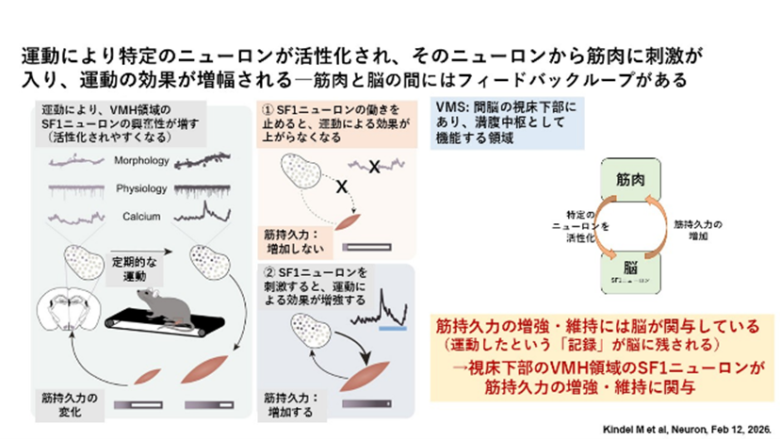

2-2)運動誘発性視床下部腹内側核ステロイド生成因子1ニューロンの活性化は持久力の向上を媒介する

反復して運動をすると、使った筋肉は量的に増加するとともに持久力が増してきますが、使わない筋肉に関しては量的に変わらず、持久力も増しません。これは運動をしたという記録がその使った筋肉に残されているからですが、それ以外にも、運動したという記録が脳に残されていて、この記録が筋肉の持久力増加に大事なのだという報告が出ています(https://www.cell.com/…/fulltext/S0896-6273(25)00989-4…)。

これはマウスを使っての実験結果ですが、マウスをトレッドミルに乗せて運動させると、運動したということが筋肉だけでなくて脳にもインプットされ、その結果、脳の特定の領域(VMH領域;満腹中枢として機能する領域)の特定のニューロン(SF1ニューロン)が刺激、活性化され、それが再び筋肉への刺激となって筋肉の持久力が増す、ということが観察されました。つまり、筋肉と脳の間には機能的なフィードバックループがあり、それを介して筋肉の持久力増加・維持がなされている、ということです。

これを支持することに、① 実験的にSF1ニューロンの働きを止めると、そのマウスにおいて運動による効果が上がらなくなる(=筋持久力が増加しなくなる)、② 実験的にSF1ニューロンを刺激すると、運動による効果が増強する、ということが観察されています。

以上のことから、筋持久力の増強・維持には脳が関与していて、運動したという「記録」が脳に残されるようです。具体的には、運動によって視床下部のVMH領域のSF1ニューロンが活性化され、それが筋持久力の増強・維持に必須の役割をする、ということです。これはマウスを使っての実験結果ですが、ヒトでもこのようなことが起きている可能性があります。高齢化や寝たきりで筋力が次第に低下してきますが、脳の特定の部位の活性化が筋持久力の向上・維持に重要だとすると、その部位をうまく活性化させることが運動療法の効果を上げるために大事なのかもしれません。あるいはスポーツ選手のパフォーマンス向上にも何かヒントとなるようなことが含まれているのかもしれません。

•脳は運動後の生理学的改善にとって重要な媒介物である

•運動はVMH SF1ニューロンへの入力を強化し、その活動を増加させる

•運動後のVMH SF1ニューロンの活性化は持久力の向上に必要である

•運動後のVMH SF1ニューロンの外因性活性化は持久力の向上を促進する

要約

反復運動は強力な生理学的効果をもたらし、人間の健康のための主要なライフスタイル介入です。運動トレーニングによる効果は、骨格筋系、心血管系、代謝系、内分泌系のリモデリングによって生じます。マウスでは、運動後の中枢神経系の活性化が、その後の持久力パフォーマンスと代謝効果に不可欠であることがわかっています。運動後は視床下部腹内側核のステロイド生成因子-1(SF1)ニューロンが活性化され、反復トレーニングは運動後のSF1ニューロンの活性化の増加をもたらします。運動トレーニングはSF1ニューロンの固有の興奮性と興奮性シナプス密度を増加させるため、運動履歴は視床下部の可塑性によってエンコードされていると考えられます。SF1ニューロンの出力を抑制すると、運動トレーニングによる持久力の向上と代謝の改善が阻害されます。逆に、運動後のSF1ニューロンの刺激は持久力の向上を促進します。これらの結果は、運動誘発性の視床下部 SF1 ニューロンの活動が、運動トレーニング後の生理学的改善の調整に不可欠であることを示しています。